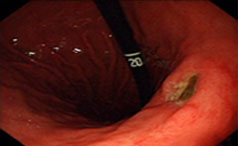

胃溃疡是指发生在胃幽门和贲门之间的慢性溃疡,是一种全球性的常见病,多发病。可发生在任何年龄段,多见于中老年人,好发于男性。胃溃疡饮食注意事项......【详情】

常见症状:体重减轻、疼痛、出血

上腹部压痛